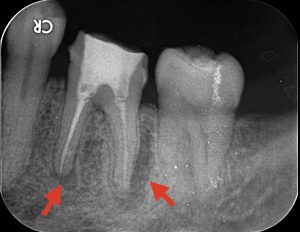

レントゲンを撮ってみると、赤い矢印部分に黒い影ができているのがお分かりいただけると思います。これは歯の根っこの先に膿が溜まっておりそれによって歯を支えている顎の骨が溶かされている状態です。根管治療は根っこの中の細菌を限りなくゼロに近づけることが大切になりますが、以前の治療で細菌や感染を取りきれなかったことにより膿が溜まってしまっています。

これは決して珍しいことではなく、一般的に行われている保険診療の根管治療では半分以上が治療失敗というデータがあり、多くの歯でこのような状況が起こっているのです。

保険診療では、使用できる材料や治療器具、治療時間などに制限があります。そのため、治療をしても治らないというのが現状です。